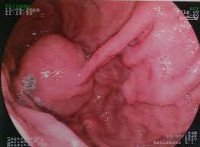

В последние годы большое значение придается эндоскопическим методикам диагностики лейомиом желудка, однако опыт показывает, что переоценивать их также не следует. Эзофагогастродуоденоскопия неинформативна при небольших интрамуральных, а также при субсерозных лейомиомах. Однако при наличии субмукозного узла эта методика является также и лечебной, так как позволяет произвести удаление новообразования во время операции. К сожалению, чаще всего интраоперационный диагноз выставляется неверно (полип желудка), и только патогистологическое исследование позволяет убедиться, что была удалена именно лейомиома желудка. При наличии изъязвленного узла с признаками распада эндоскопическая биопсия проводится обязательно для дифференциальной диагностики с раком желудка.